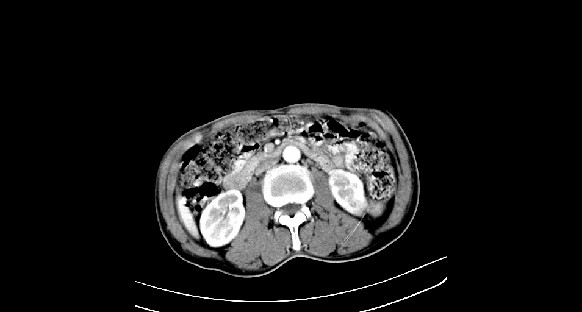

男性,70岁,体检b超发现左肾占位,请各位战友发表一下观点

左肾有两个病灶,且较大的病灶内可见点状钙化灶,增强扫描边缘也是呈渐进性强化,中央部分未见明显强化